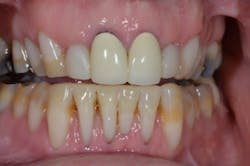

Next, we are ready to transfer the information from the wax-up to the mouth using a series of putty stents and guides to fabricate the provisional restorations (more details are listed below). During this step, we work out the finer details of design using phonetics and arc of closure to refine edge position and lingual contour.

Once the patient is completely comfortable and happy with the provisionals, we take a new set of photos, facebow, bite registration, and models to communicate with the ceramist, who will complete the fourth version of the case—in porcelain.

3. Do a mock-up and equilibrate before prepping; double-check your reduction with a guide. The mock-up helps you and your patient visualize the intended results before taking an irreversible step. It also lets you make your depth cuts from the final contour, rather than the existing shape of the teeth. Doing a rough equilibration at this point makes the provisional stage much easier. Remember, the mock-up is a duplicate of your planned results.

5. Make necessary occlusal adjustments on the opposing arch once the first arch is idealized. The mock-up and provisionals are the blueprints for the final restorations, determined before ever picking up a handpiece. Once these are transferred to the mouth, make your adjustments to the opposing arch to provide a balanced occlusion for this treatment phase. This way, when you restore the second arch, your occlusal stops will already be established. You will still need to adjust the upper incisors for proper phonetics as well as horizontal and vertical position. Proper treatment planning gets us close to the ideal position, but there is no substitute for seeing the provisionals in the mouth.